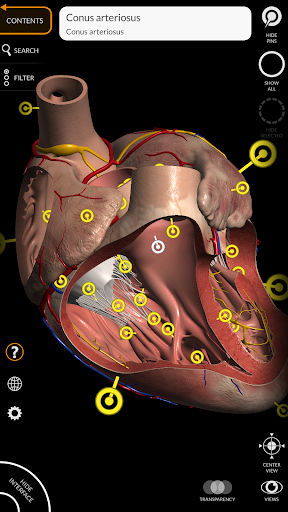

Các mô hình giải phẫu 3D đặc biệt chi tiết và có kết cấu lên đến độ phân giải 4k.

MÔ HÌNH GIẢI PHẪU 3D

• Hệ thống tim mạch

• Xoay và phóng to từng mô hình trong không gian 3D

• Tùy chọn ẩn hoặc cô lập một hoặc nhiều mô hình đã chọn

• Bộ lọc để ẩn hoặc hiển thị từng hệ thống

• Bằng cách chọn một mô hình hoặc một ghim, thuật ngữ giải phẫu liên quan sẽ hiển thị